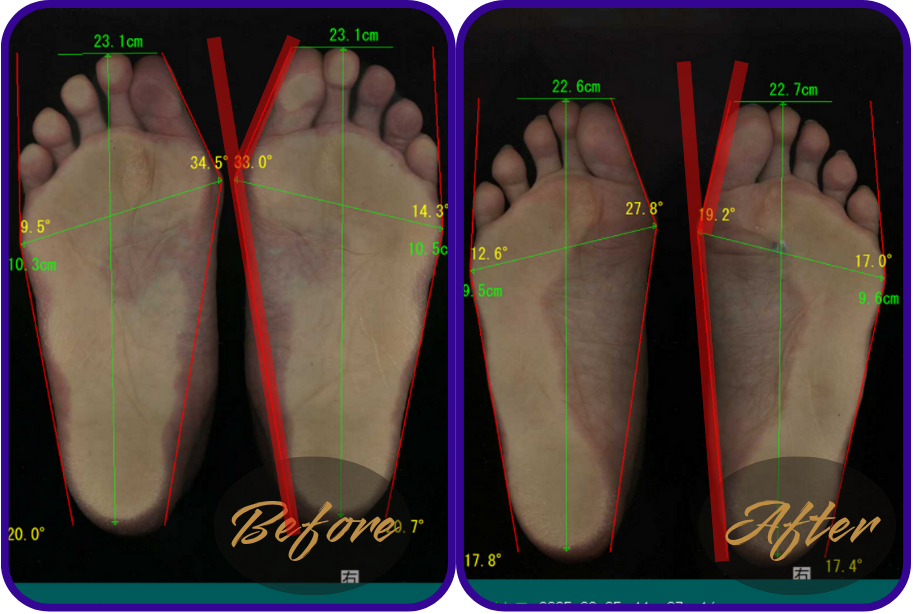

姿勢や歩き方の改善判断は、足裏の圧力画面や外反母趾の数値で出します。

ダイエットと同じで、体重やサイズを数値でみないとダイエットに成功したかわからないですものね。

↑39,5°あった外反母趾が27,7°まで改善。

↑足幅10,9㎝あったのが9,7㎝まで細くなった。

歩行整体に通われた患者様の足裏の様子をご紹介します。

※テーピングやゴムバンドなどは使用しておりません。整体と姿勢歩き方レッスンのみです。

足の横幅が自分で見ても細くなった

↑50代女性

お悩み…膝の痛み。

感想…「膝の痛みはなくなった。実は腰痛もあったのに、なくなった。とにかく足の形が良くなった!」